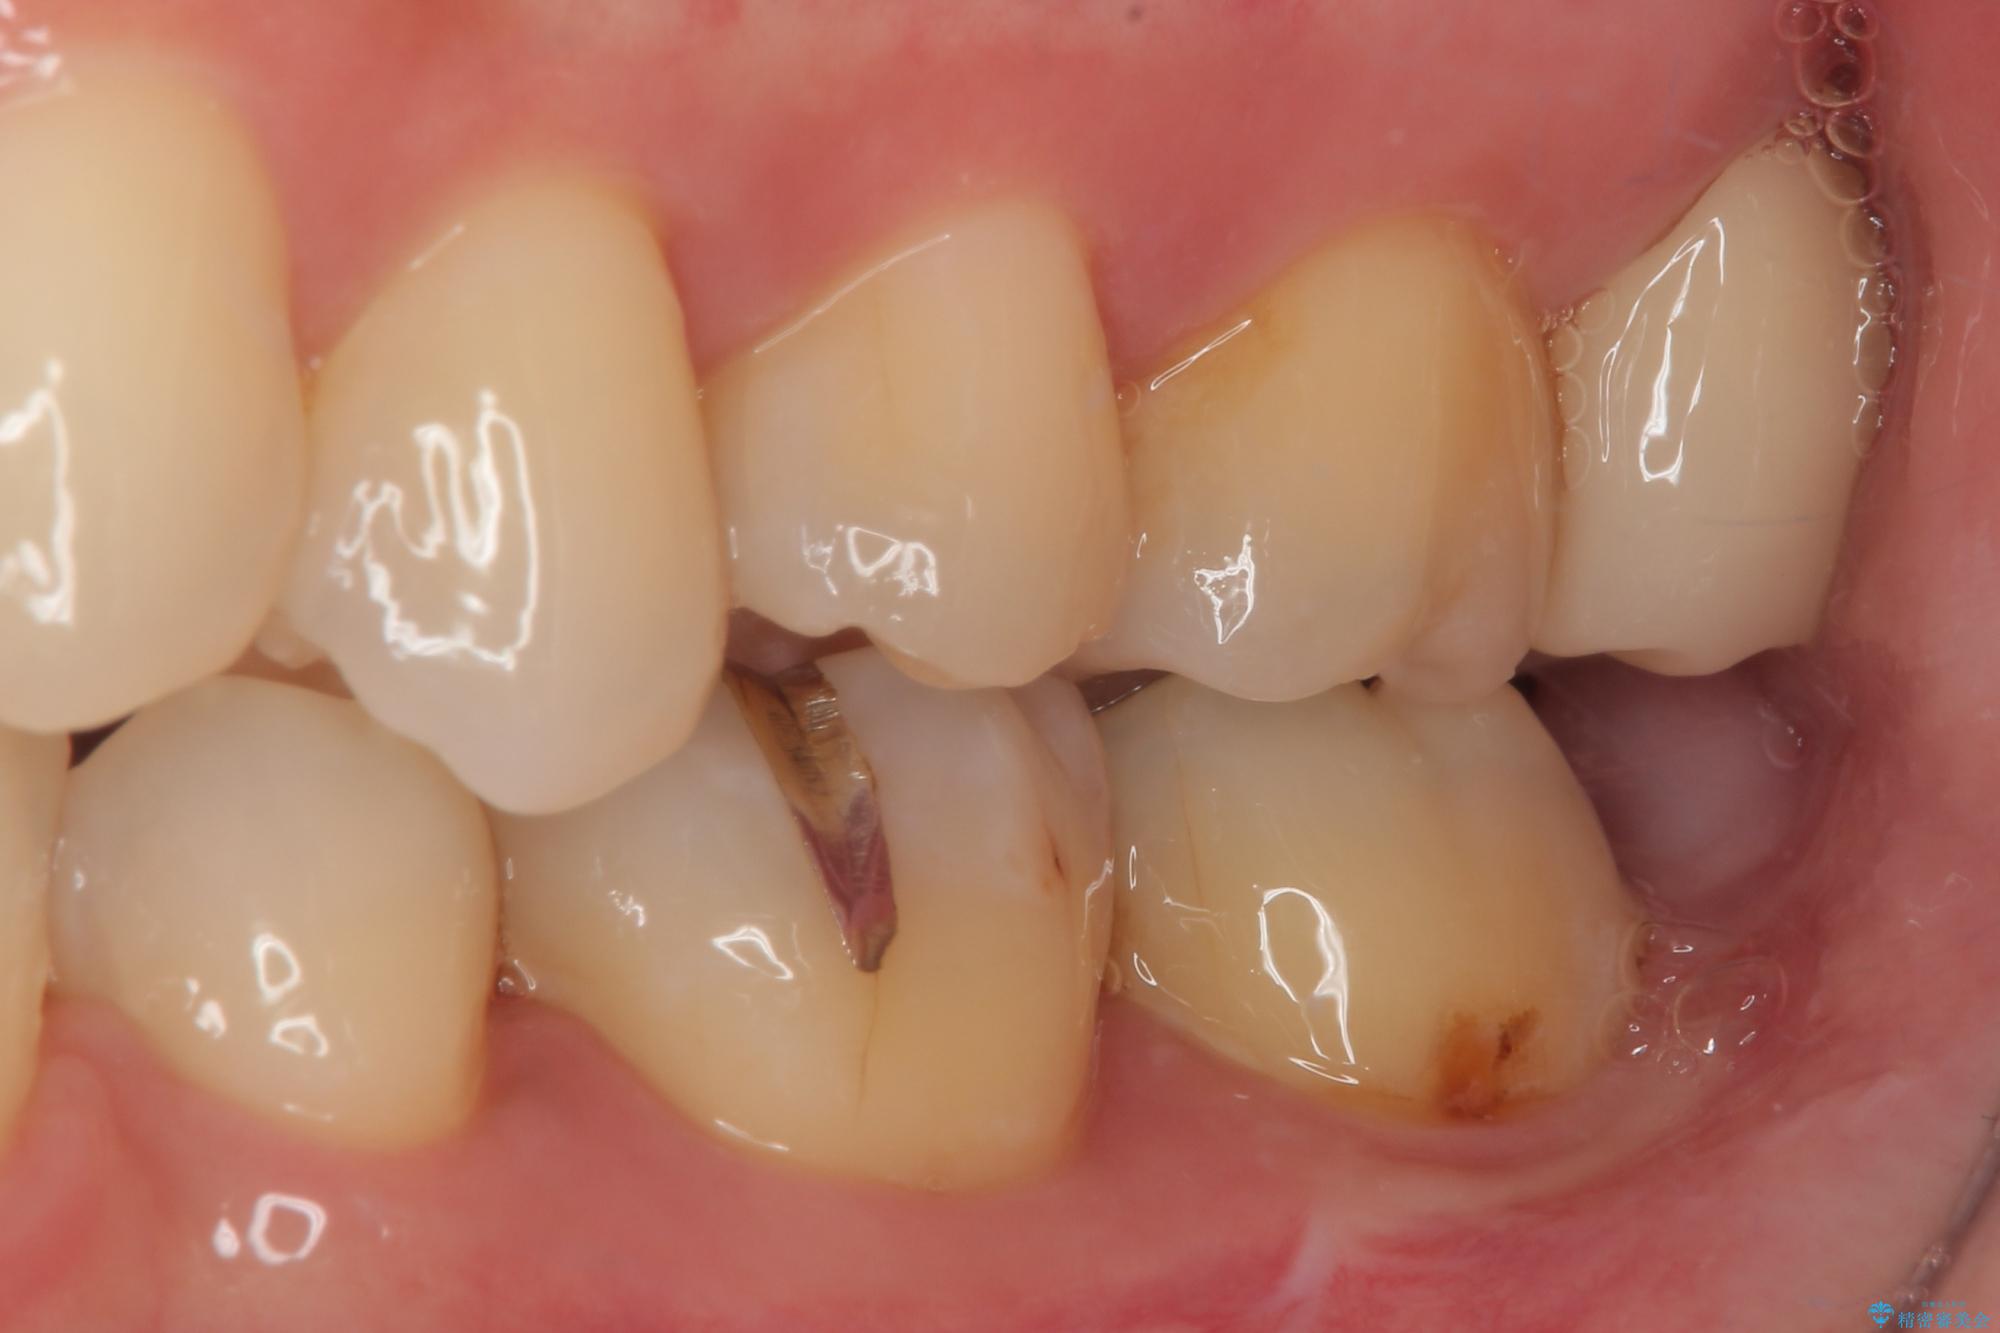

- 元々むし歯があったものの、処置が困難とのことでしたが、矯正治療を終えたので処置をしたいとのことで来院された患者様です。

左右ともに最後臼歯が頬側に顕著に突出しており、むし歯になってしまったことが想像されました。

矯正治療により処置が可能な位置に歯が移動したため、オールセラミッククラウンにて補綴治療を行うこととしました。

歯列が移動したとはいえ、左右ともに後方傾斜しており、むし歯の除去、形成(形を整える)、型取りの全てが非常に困難な処置となりました。